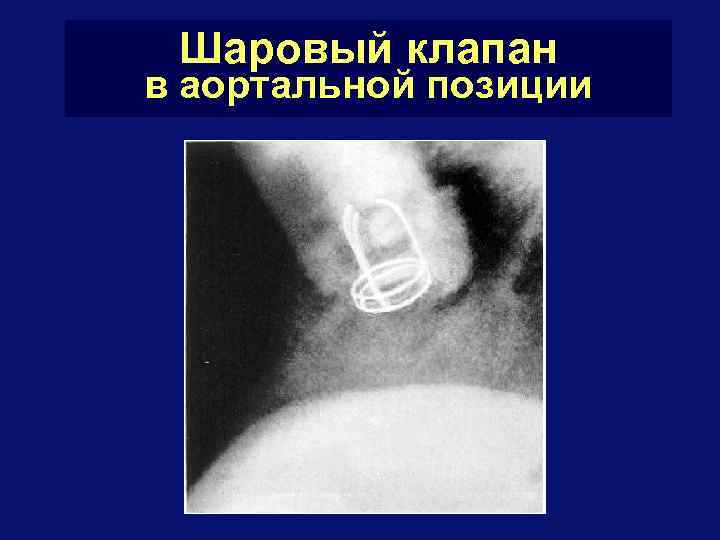

Шаровые и дисковые клапаны

Шаровый клапан в аортальной позиции